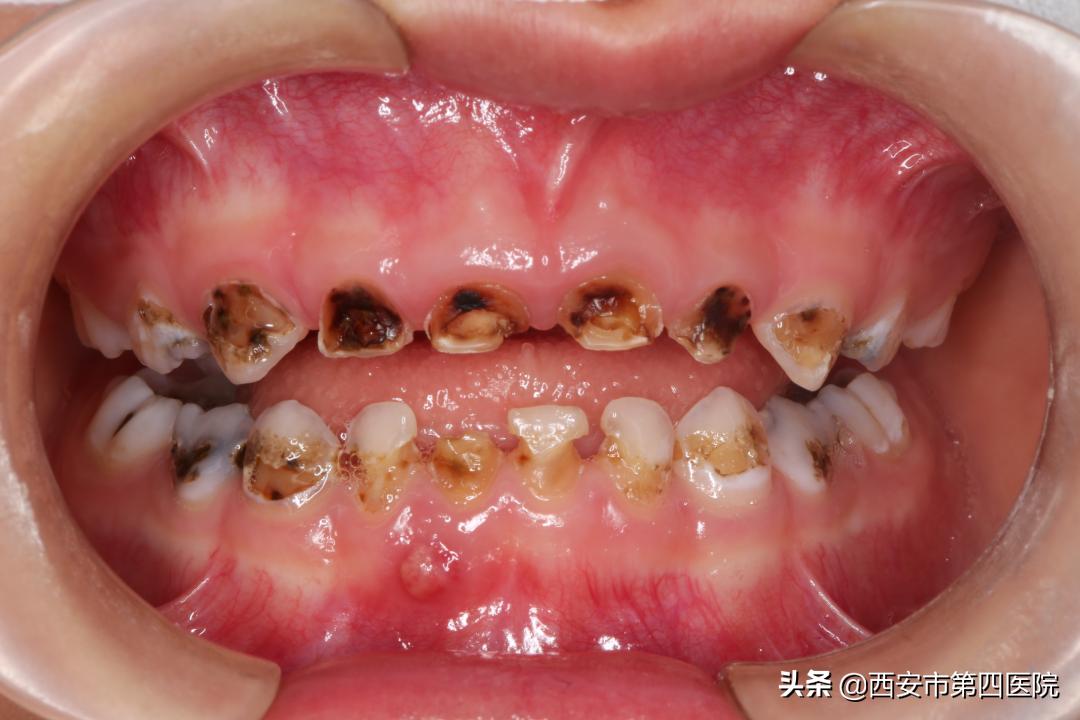

01 重度龋齿 孩子疼痛不愿意进食

5岁的辰辰(化名)由于口腔卫生习惯不佳,一年前就开始有了龋齿。

后续发展到口内存在多个虫牙,等到3个月前,已经出现了牙齿疼痛、牙龈肿起脓包等现象,辰辰妈妈带着去医院就诊。

口腔科葛鑫主任详细询问病史,全面检查辰辰口内情况,确诊是重度婴幼儿龋,并提出全身麻醉下口腔综合治疗的方案。

(左图为术前,右图为术后)